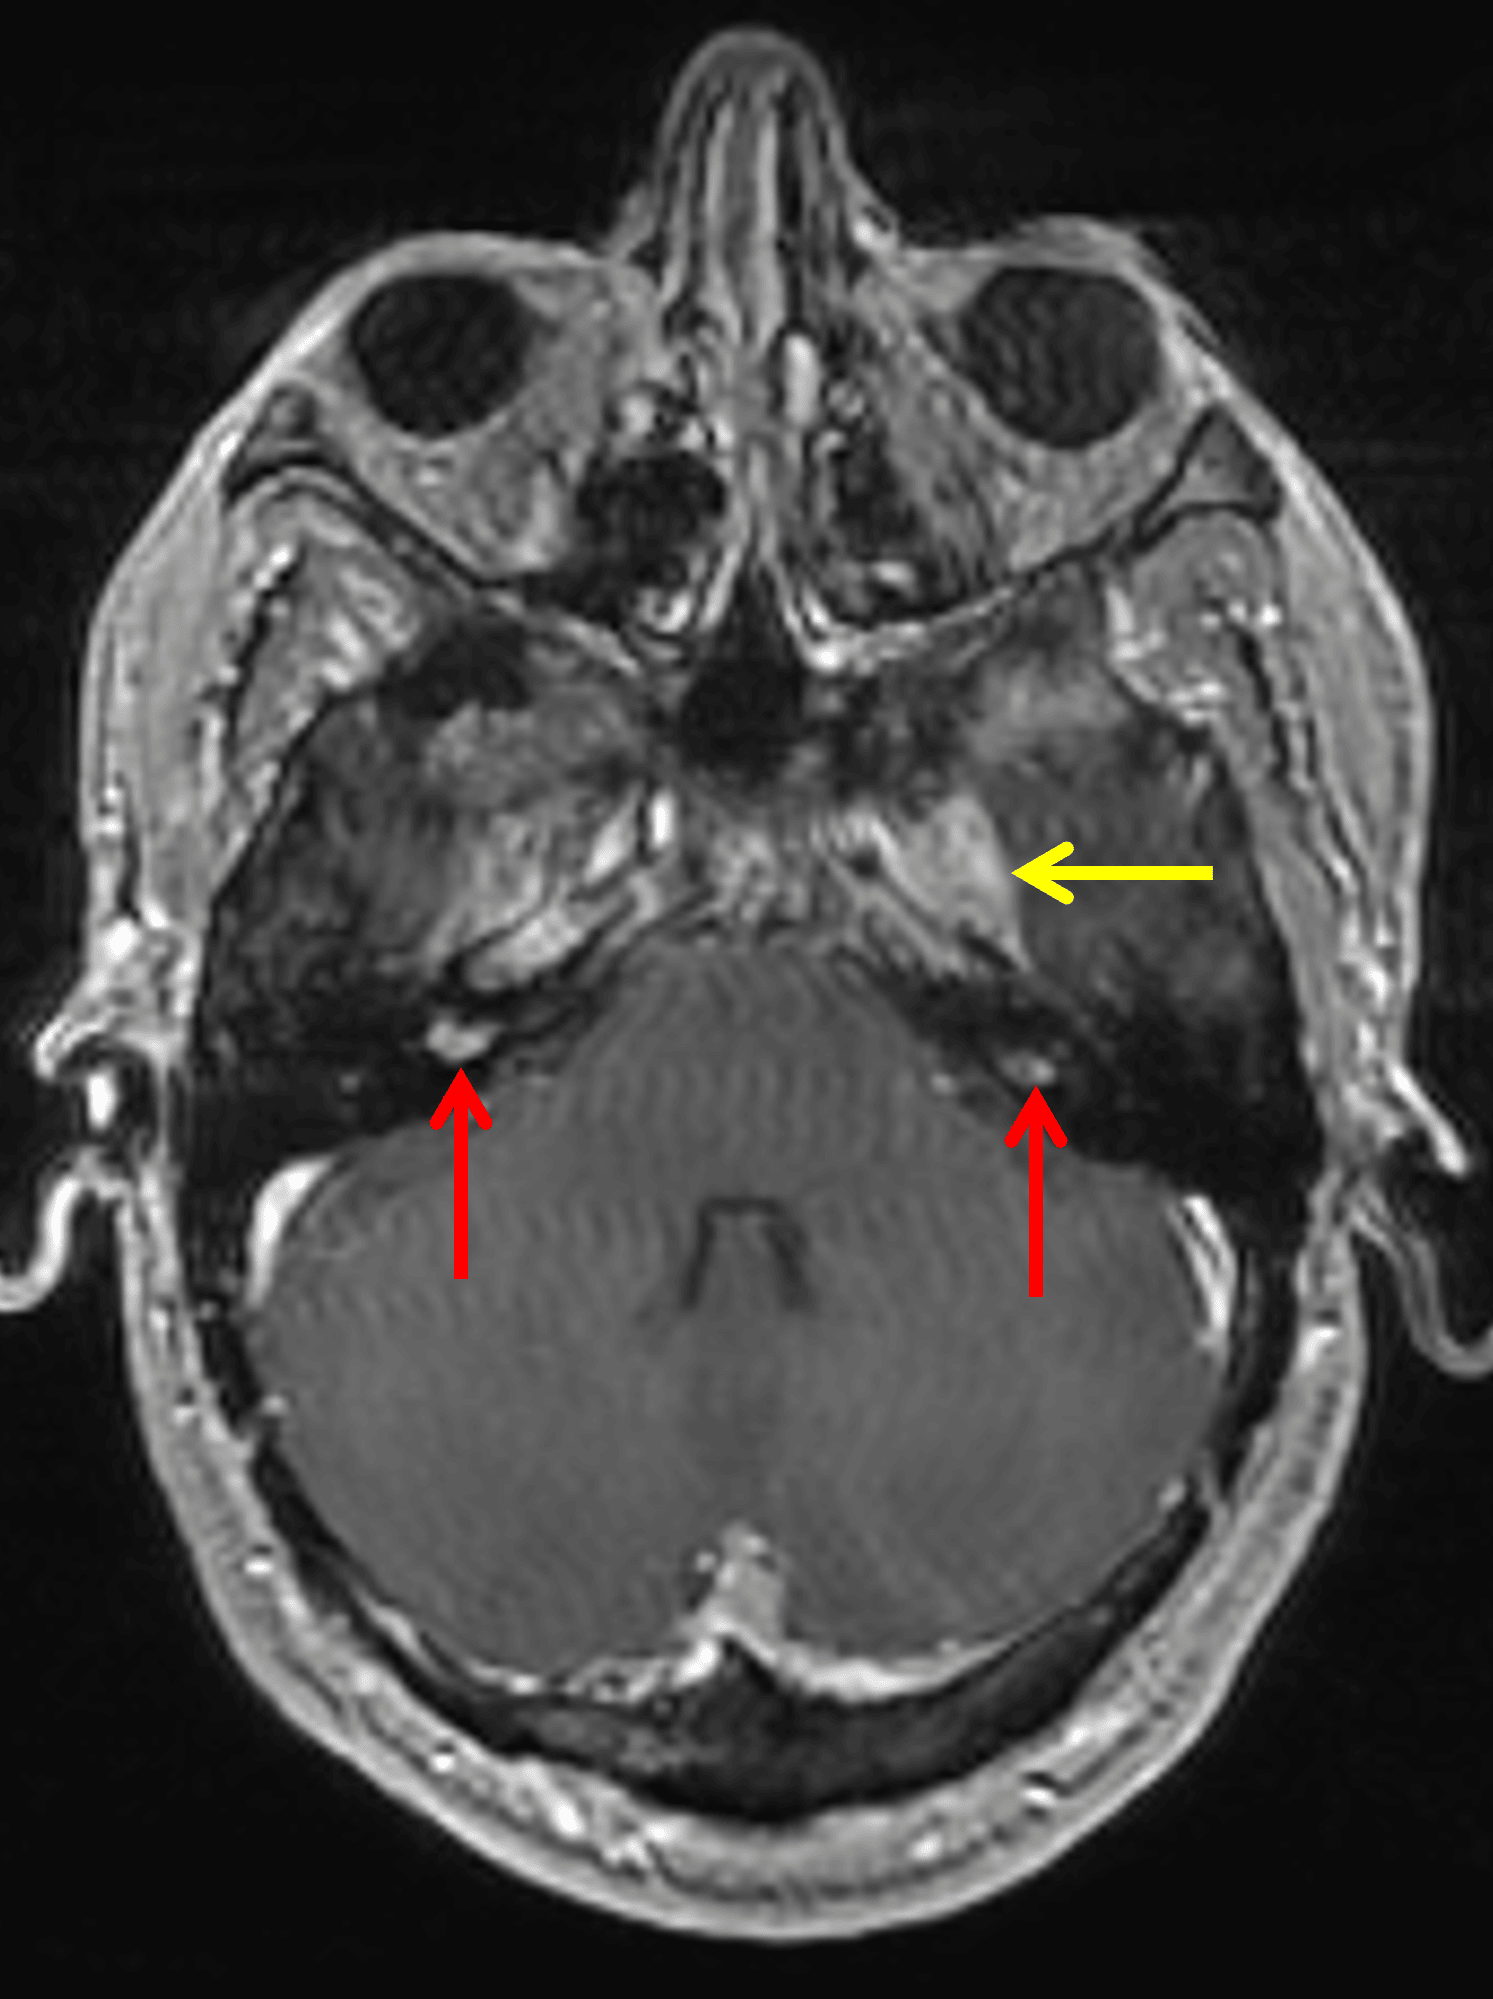

Bilateral vestibular schwannomas (red arrows). Enhancement in the left Meckel's cave extending into the foramen ovale (yellow arrow), also likely a schwannoma.

• Enhancing lesions in the bilateral internal auditory canals, larger on the right

• Enhancing soft tissue in the left Meckel's cave extending into the left foramen ovale